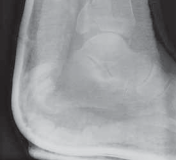

A B C FIG 3•

Radiographic evaluation with an ankle trauma series: AP (

A

), lateral (

B

), and mortise (

C

) views.

(continued)